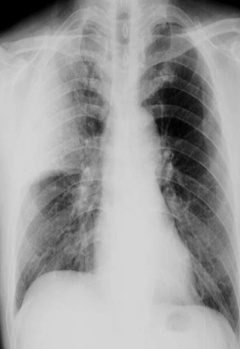

图中可见右上叶“一片白”,根据公式诊断为右上叶大叶性肺炎